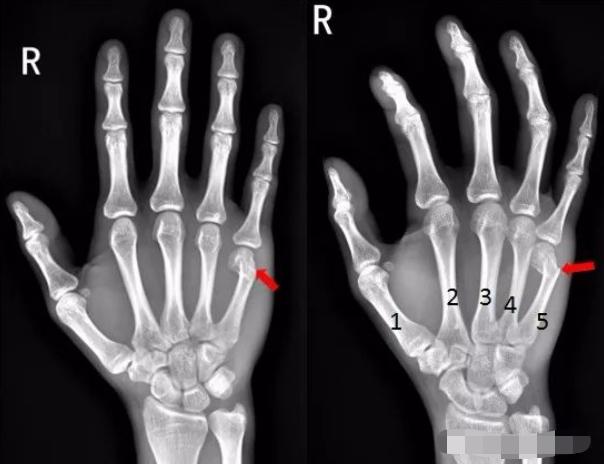

5、患者酒后右手砸墙,拍片如下:

右手第五掌骨远端骨皮质不连续,骨折端移位、成角。右手第五掌骨骨折(1-5. 第1-5掌骨)

6、患者右手被车门挤压,拍片如下:

右手第四掌骨中段、第五掌骨基底部见横行骨折透亮线,骨折端对位对线尚可,第四、第五掌骨骨折。